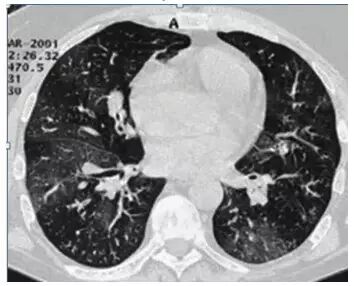

2. 马赛克灌注(Mosaic perfusion)

这是肺内通气灌注不一致的表现,主要是小支气管炎症导致肺内局部积气,像马赛克拼图一样